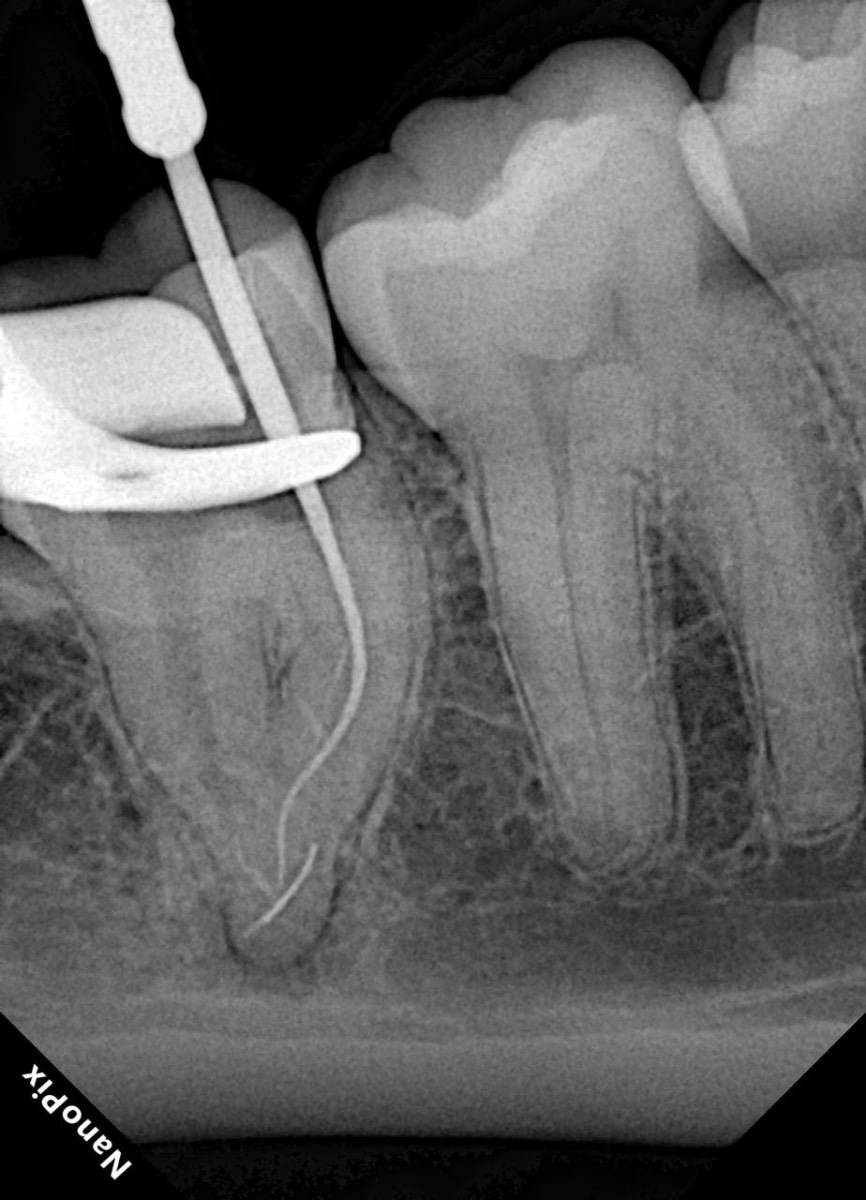

Гарриевич Опубликовано 31 января Автор Поделиться Опубликовано 31 января Когда в твоем кресле оказывается пациент с редким заболеванием «стоматолог-терапевт» работать всегда… легче. Именно! Потому что ты на 100% уверен, что этот человек понимает разницу между «гарантия» и «прогноз», а он на 100% уверен, что ты тот кто ему нужен. Зуб 4.7 со сложной анатомией, ступенькой в мезиальной системе, двойным изгибом, пропущенным каналом и апикальным периодонтитом. Реколл 1 год И сам осмотр через 1 год 4 1 1 Ссылка на комментарий

Гарриевич Опубликовано 2 февраля Автор Поделиться Опубликовано 2 февраля @Carioznik да, им проще сглаживать ступень, проходить длинные каналы, в дистальном отделе удобнее фиксировать файл 1 1 Ссылка на комментарий